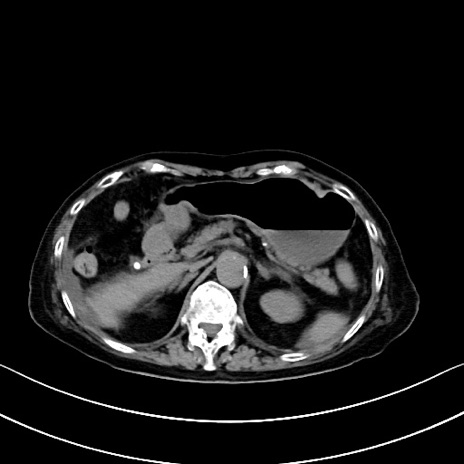

横断像

他院CT